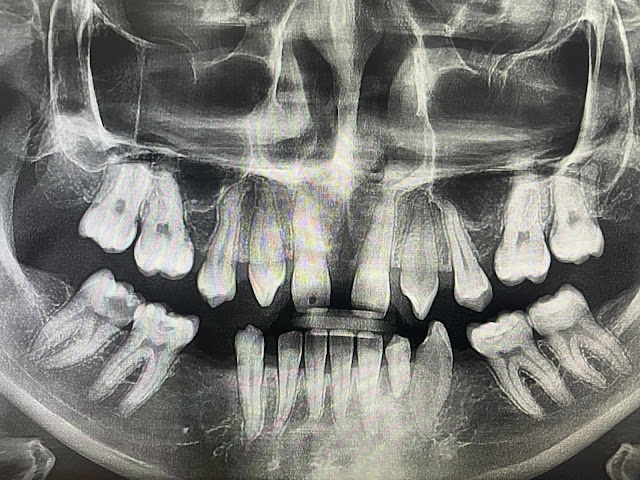

Klinik Pergigian Syarifah - KPS Dentalcare: Penyelesaian Hypodontia untuk Gigi Tidak Berkembang